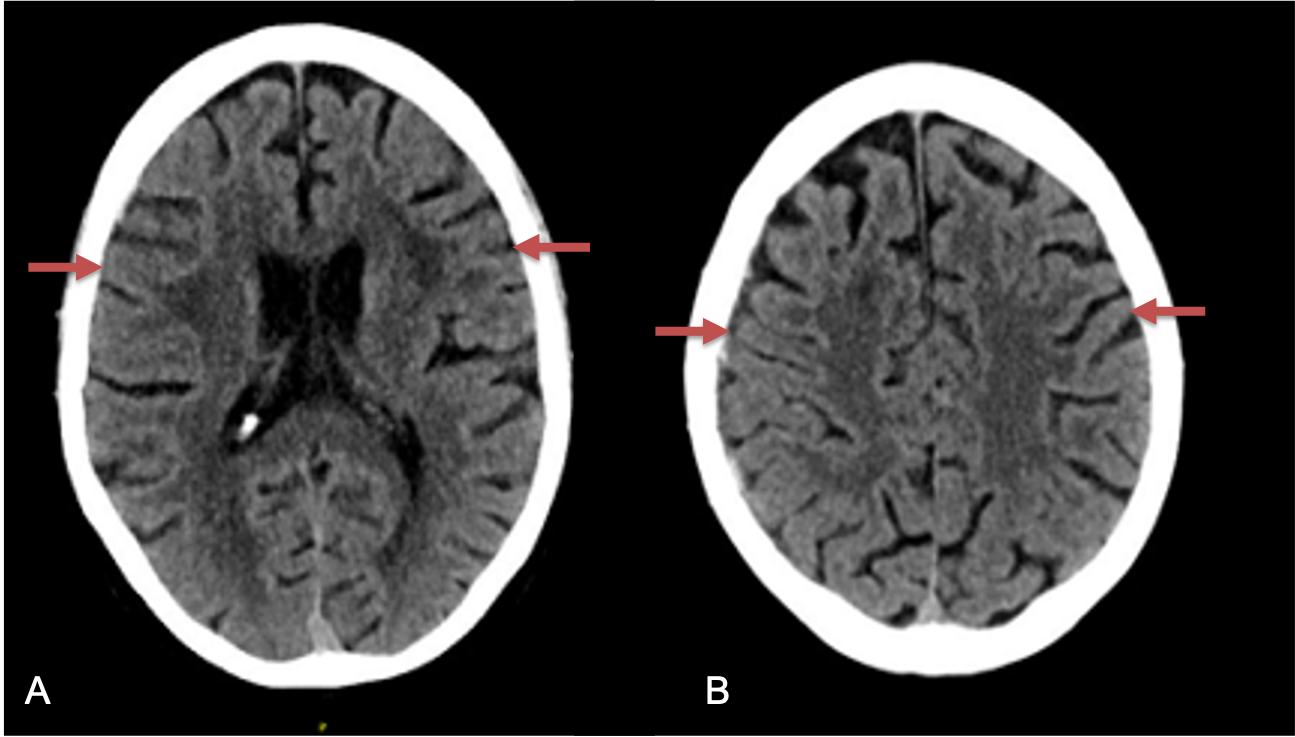

The patient agreed to receive minimally invasive treatment with Bilateral Middle Meningeal Artery Embolization, a new approach to promote resorption of chronic and subacute subdural hematomas in patients that are not improving with conservative measures or have contra-indications to surgical evacuation. Selective catheterization of the Middle Meningeal Artery is followed by transarterial embolization of the territory and inflammatory membranes that are felt to be secreting serosanguinous proteinaceous exceeding the capacity for resorption. MMA embolization was performed bilaterally in this patient. (Figure 2. A and B)

Figure 2. A) Initial right ECA angiogram ; B) Post MMA Embolization; C) Selective Embolization Of Middle Meningeal Artery Membranes using PVA particles (arrows)